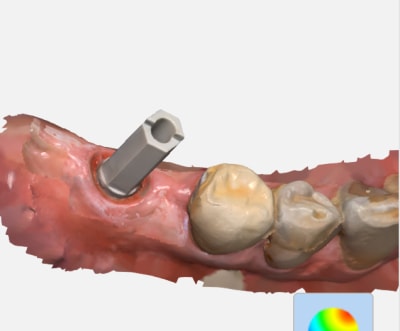

Certains d’entre vous ont ils essayé ce type d’ic usiné fibré ?

J’ai reçu un disque pour faire des tests d’usinage ... c’est concluant de ce point de vue.

Reste à savoir s’il peu susciter l’interet au fauteuil .. ( ic issue de ios biensure ) donc ajustage en bouche sans problèmes.

On dirait un inlay core en PEEK.

J'en fais depuis 4/5 ans, ça a l'air de tenir la route mieux que les tenons fibrés mais c'est NR.... en attendant l'interdiction des alliages Co Cr

Attention ! Tout est fibré ! Pas juste le tenon ..

Ce n’est pas comme un tenon fibré recouvert d’un compo qui se desolidariserait lors d’une retouche pour extraire l’ensemble ..